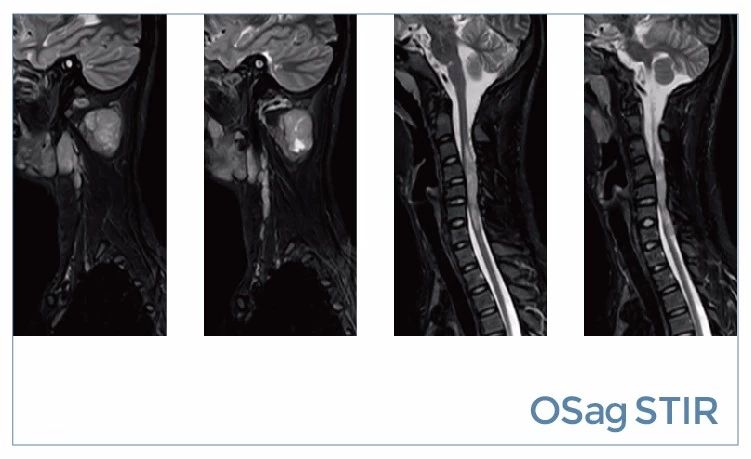

【朗润影像档案】20190816磁共振影像病例结果讨论